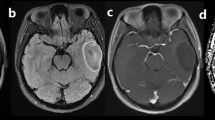

Included were 71 glioma patients (mean age, 50.17 ± 13.38 years; 35 men). HM-MRI images were collected at five different echo times (80–200 ms) with seven b-values (0–3000 s/mm2). A modified three-compartment model with very-slow, slow and fast diffusion components was applied to calculate HM-MRI metrics, including fractions, diffusion coefficients and T2 values of each component. Pearson correlation analysis was performed between HM-MRI derived fractions and H&E staining derived percentages. HM-MRI metrics were compared between high-grade and low-grade gliomas, and between IDH-wild and IDH-mutant gliomas. Using receiver operational characteristic (ROC) analysis, the diagnostic performance of HM-MRI in grading and genotyping was compared with mono-exponential models.

HM-MRI metrics FDvery-slow and FDslow demonstrated a significant correlation with the H&E staining results (p < .05). Besides, FDvery-slow showed the highest area under ROC curve (AUC = 0.854) for grading, while Dslow showed the highest AUC (0.845) for genotyping. Furthermore, a combination of HM-MRI metrics FDvery-slow and T2Dslow improved the diagnostic performance for grading (AUC = 0.876).